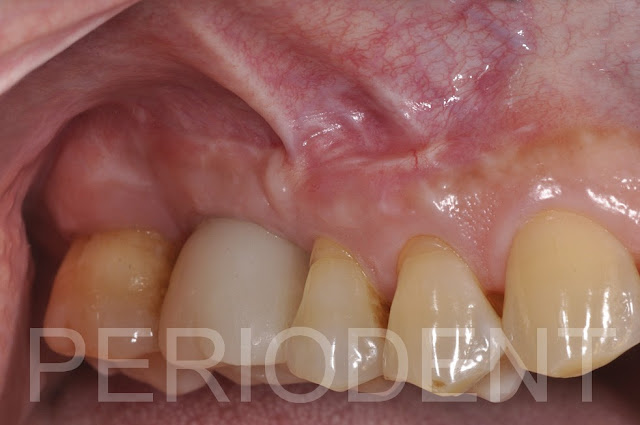

拆線時